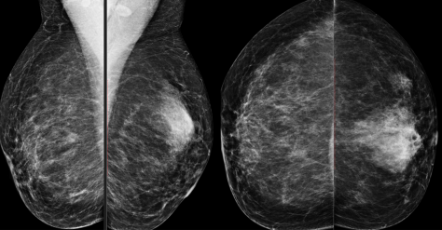

Dê o BI-RADS

5: prestar atenção no contorno branco com estrela

Sem o contorno branco é 4